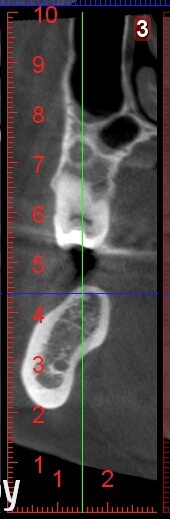

lonely_jack Опубликовано 14 ноября, 2014 Поделиться Опубликовано 14 ноября, 2014 Здравствуйте, коллегиВчера устанавливал имплантат в область 46 зуба. Планировал по КТ, челюсть немного "вертолет", но 10 мм имплант должен был встать нормально. Сегодня пациентка пришла с отеком в этой области и жалобами на немного затрудненное глотание. Вчера болело у нее, сегодня нет. Во время операции особо ничего не кровило. Как один из вариантов предполагаю перфорацию язычной кортикалки и повреждение артерии.Вопрос к тем, кто сталкивался с подобным - как вести пациента? Что то особенное нужно назначать, кроме антибиотиков? КТ повторно пока нет возможности сделать.ось импланта примерно соответсвует оси на картинке. Ссылка на комментарий

lonely_jack Опубликовано 14 ноября, 2014 Автор Поделиться Опубликовано 14 ноября, 2014 Ок, спасибо, перфорировал кортикалку скорее всего при первом пилотном сверлении, потому что было чувство, что провалился, потом чуть угол изменил, т.е. по другой оси пилотом прошел, туда и поставил. Будем наблюдать Ссылка на комментарий